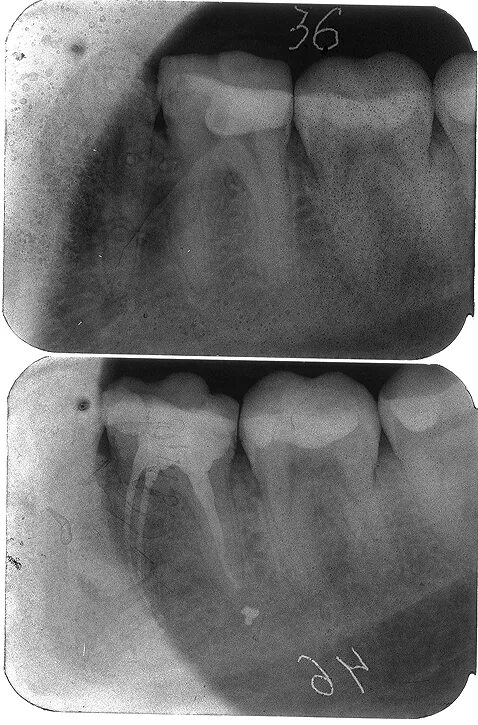

Зубы слева